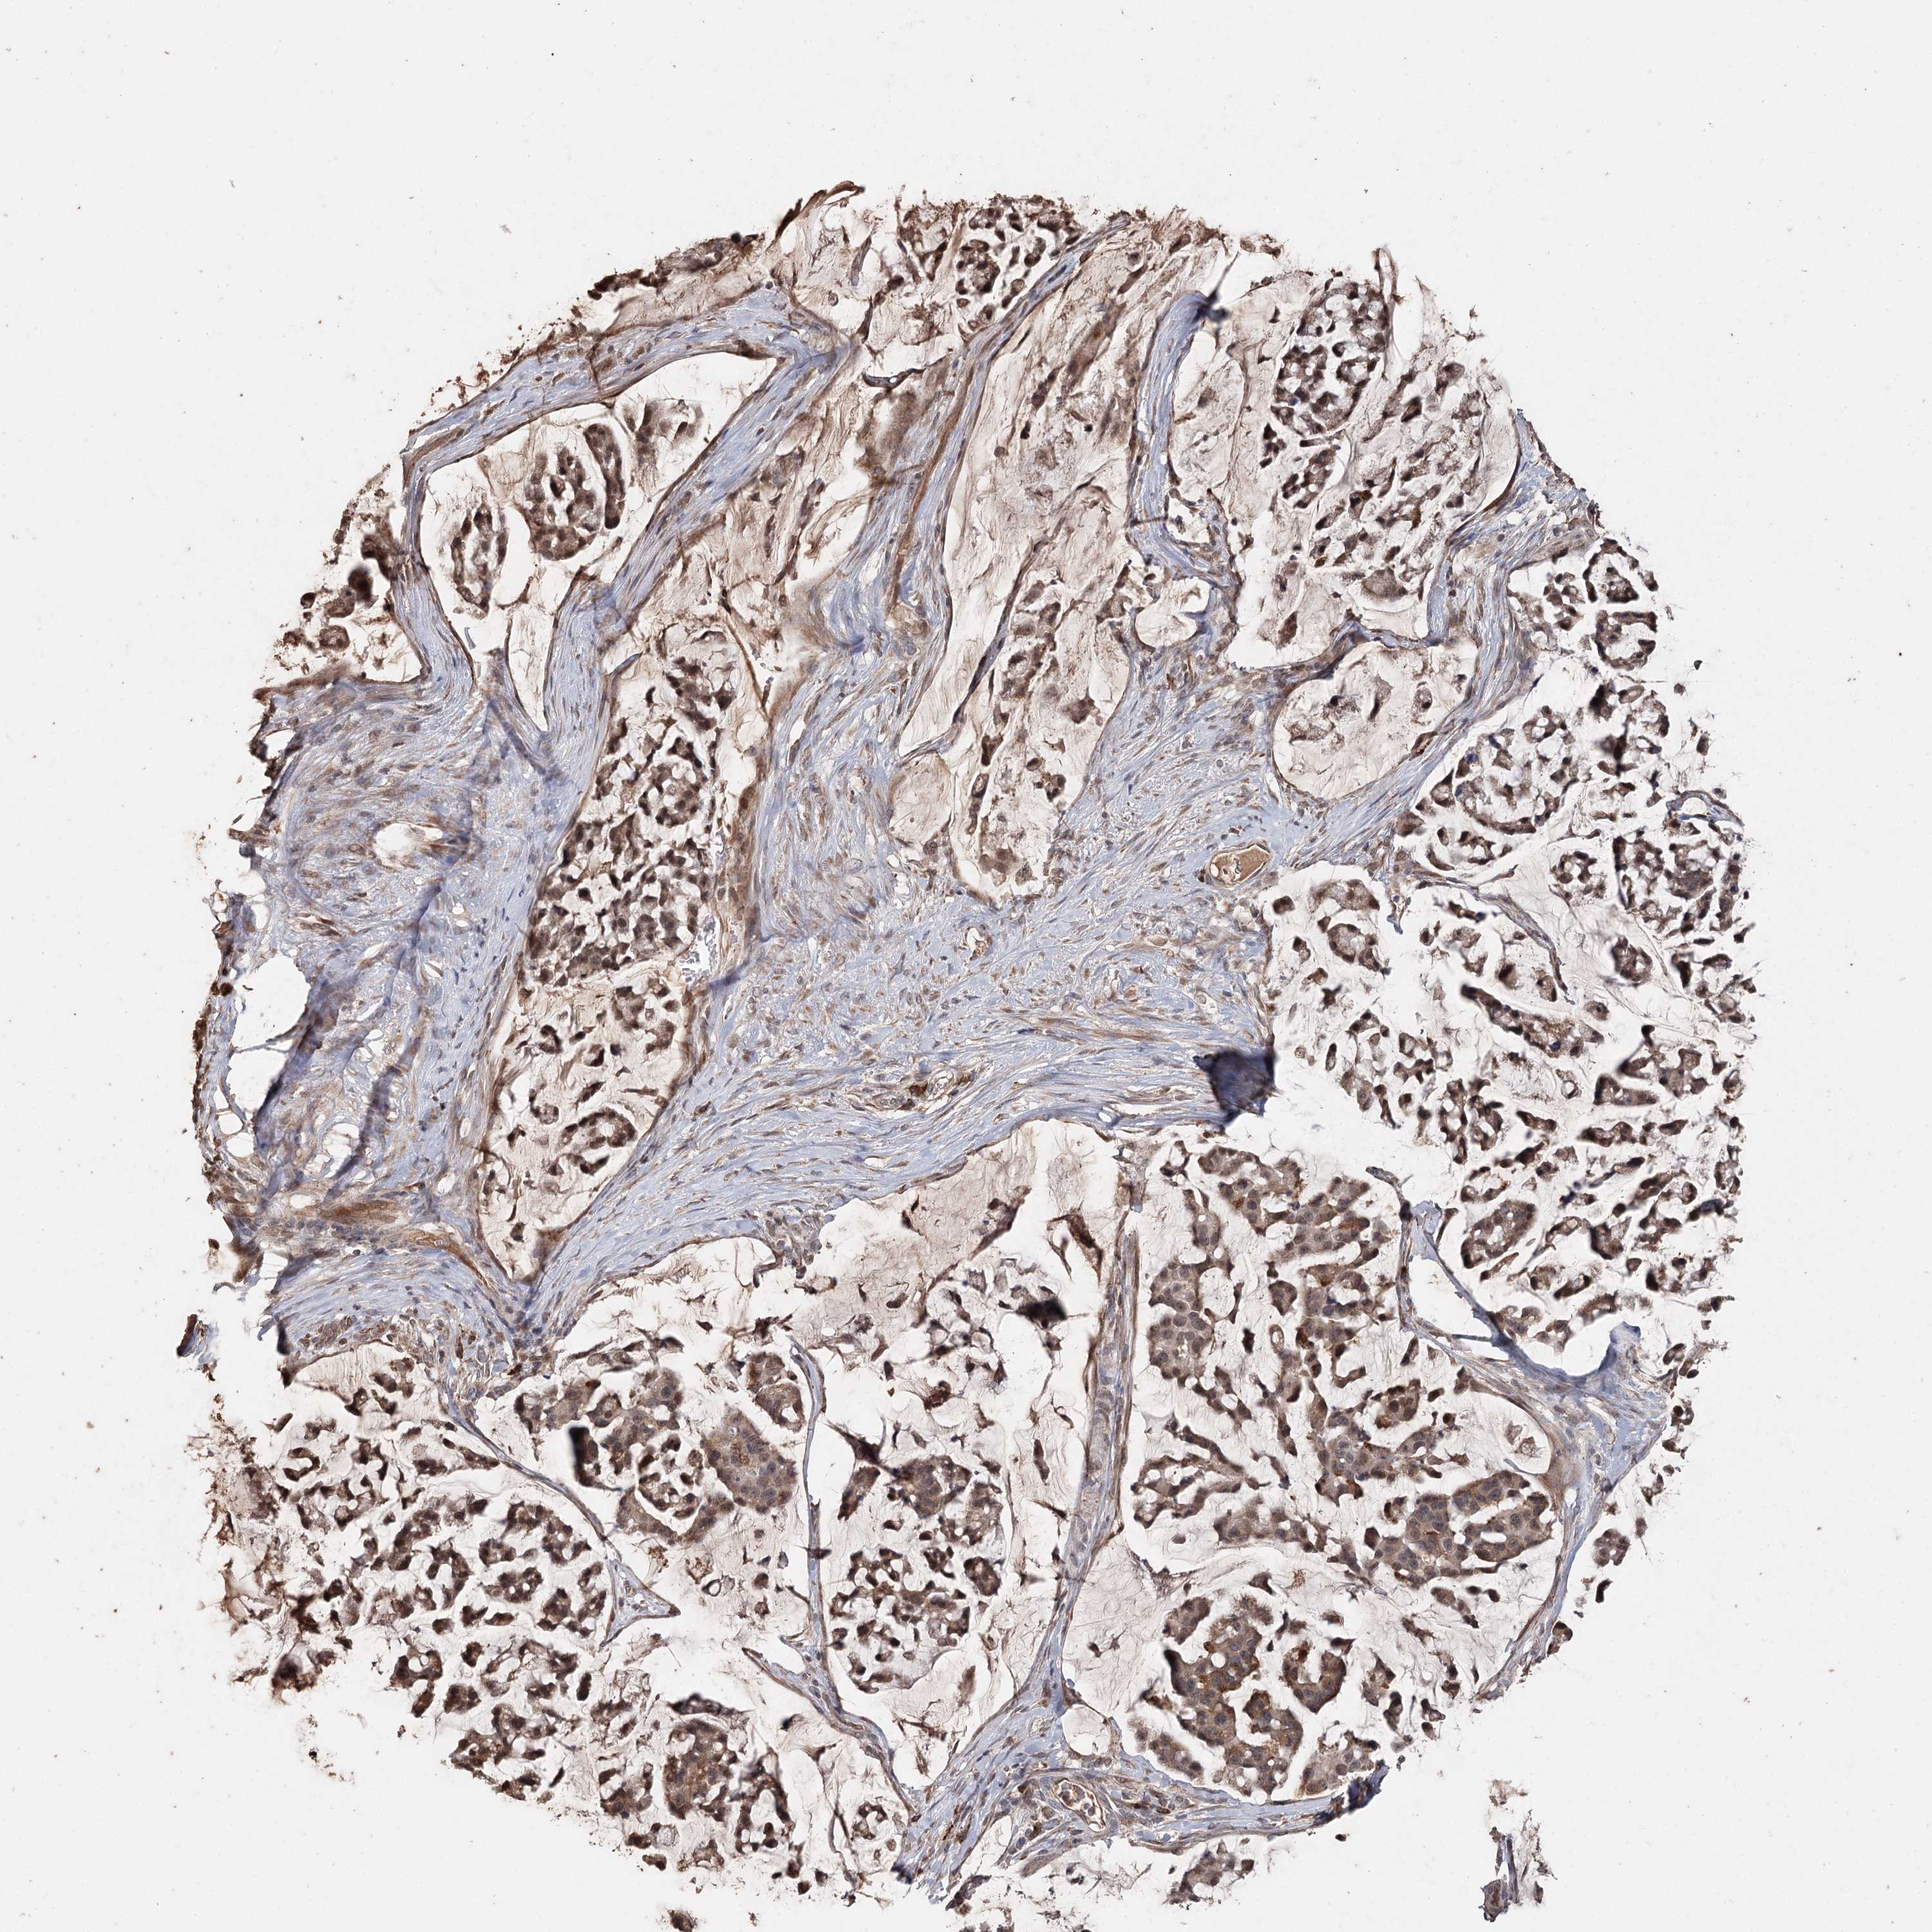

STOMACH CANCER - Protein expressioni

A mouse-over function shows sample information and annotation data. Click on an image to view it in a full screen mode. Samples can be filtered based on level of antibody staining by selecting one or several of the following categories: high, medium, low and not detected. The assay and annotation is described here.

Note that samples used for immunohistochemistry by the Human Protein Atlas do not correspond to samples in the TCGA dataset.

Antibody stainingi

Antibody staining in the annotated cell types in the current human tissue is reported as not detected, low, medium, or high, based on conventional immunohistochemistry profiling in selected tissues. This score is based on the combination of the staining intensity and fraction of stained cells.

Each image is clickable and will lead to virtual microscopy that enables deeper exploration of all samples and also displays staining intensity scores, fraction scores and subcellular localization as well as patient and tissue information for each sample.

Antibody HPA005480

Antibody HPA024300

Antibody CAB037030

Staining

High

Medium

Low

Not detected

Intensity

Strong

Moderate

Weak

Negative

Quantity

>75%

75%-25%

<25%

None

Location

Nuclear

Cytoplasmic/membranous

Cytoplasmic/membranous,nuclear

Adenocarcinoma, NOS

Adenocarcinoma, High grade